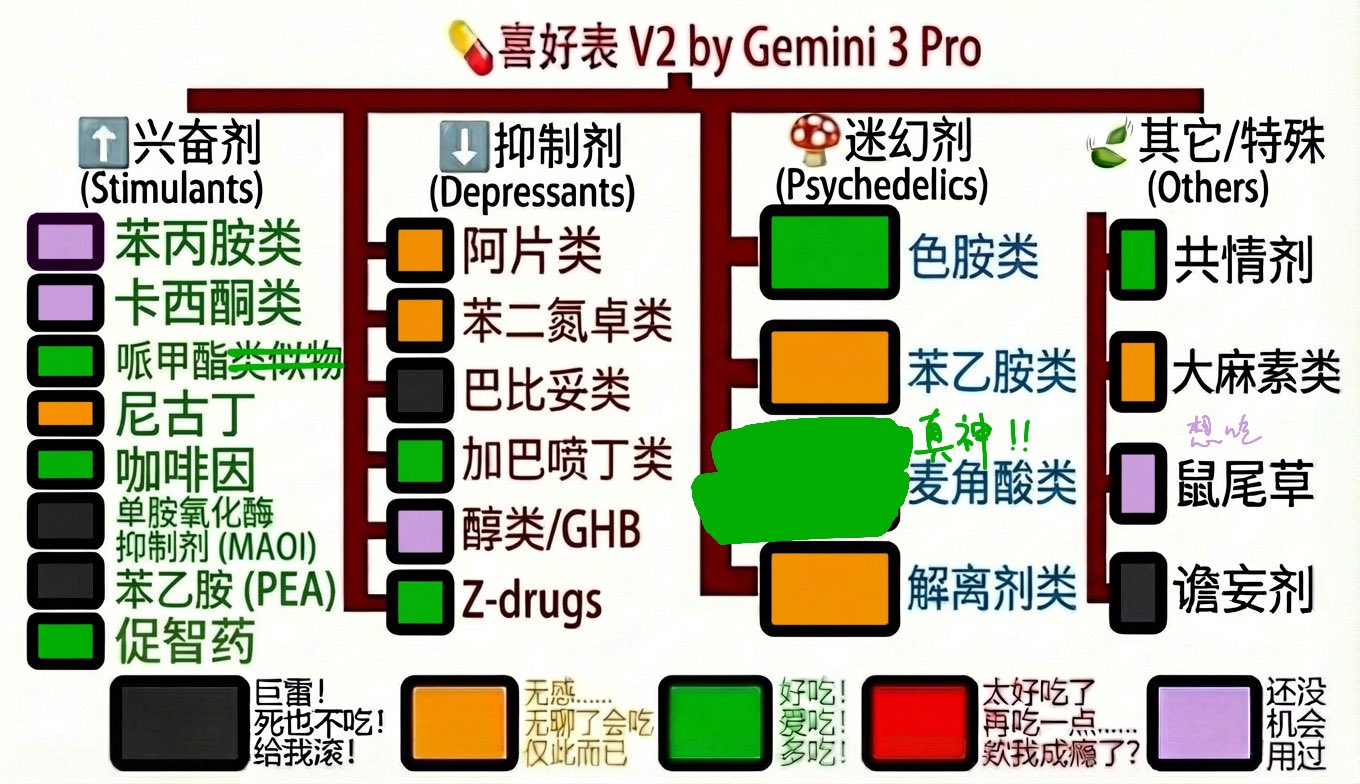

*被兴奋剂创过太多次以至于只敢吃医用剂量

*bzd/z离开了你我怎么活(睡)啊

*解离剂抗抑郁太棒了,就算没有长期效果那几个小时也能喘口气

*致幻剂要不是自带防沉迷机制我...

*谵妄。。这玩意不配上表撵下去 https://t.co/xuBMh2IXl5

无名 @dDguwkiRkZcCSrt@AnIncandescence 捉虫,左边加巴喷丁是红色,右边加巴喷丁是绿色

炽烈已极 @AnIncandescence@dDguwkiRkZcCSrt 喔可能是因为右表比较细当成加巴喷丁本体了()

炽烈已极 @AnIncandescence普瑞巴林你唯一一盏红灯...

mimeng mimeng @MMimeng72886@AnIncandescence 🤔共情剂类有哪些药物

炽烈已极 @AnIncandescence@MMimeng72886 比如5-mapb,6-apb

炽烈已极 @AnIncandescence@MMimeng72886 比如5-mapb,6-apb,mdma

Anoko @fawpv25@AnIncandescence 诶,苯乙胺类和色胺类差别很大吗?其实我没吃出特别大的差异(((

炽烈已极 @AnIncandescence@fawpv25 有,我感觉差别挺大的....怎么说呢,吃多了就能总结规律看出这仨致幻剂的区别了(草)